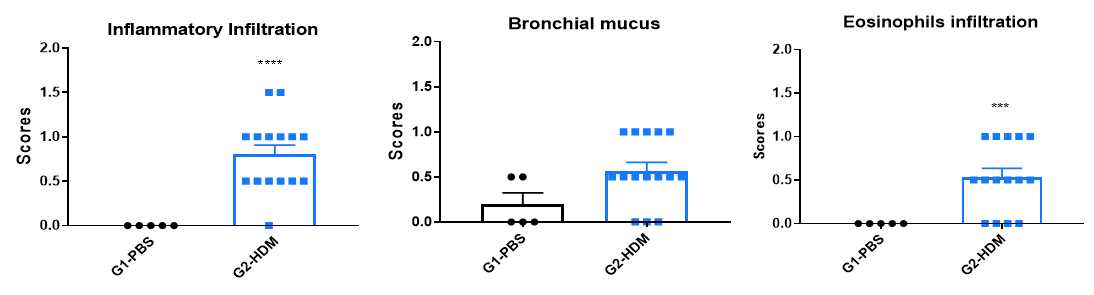

Airway Histology in Asthmatic Mouse Model

OVA successfully induces asthma-related pathology in wild-type C57BL/6 mice. H&E staining of lung tissue shows asthma-related pathology in OVA-treated (G2) mice, including vascular and peribronchial inflammation (b) and mucus (a) accumulation in some bronchi, compared to the untreated (G1) group.

H&E staining of lung tissue in HDM-induced asthmatic C57BL/6 mice. Compared to G1 controls, G2 mice treated with house dust mite (HDM) exhibited characteristic asthma pathology, including vascular and peribronchial inflammatory cell infiltration (b) and mucus production (a). These findings confirm that HDM successfully induces asthma in wild-type C57BL/6 mice.

H&E staining of lung tissue in HDM-induced asthmatic mice. Compared to G1 (C57BL/6) and G3 (B-hIL4/hIL4RA) untreated controls, G2 (C57BL/6) and G4 (B-hIL4/hIL4RA) mice treated with house dust mite (HDM) exhibited hallmark asthma pathology, including peribronchial and perivascular mixed inflammatory cell infiltration (b) and mucus accumulation (a) in the bronchi. Dupilumab treatment significantly reduced these pathological features, demonstrating the therapeutic efficacy of anti-IL-4R blockade in an HDM-induced allergic asthma model.